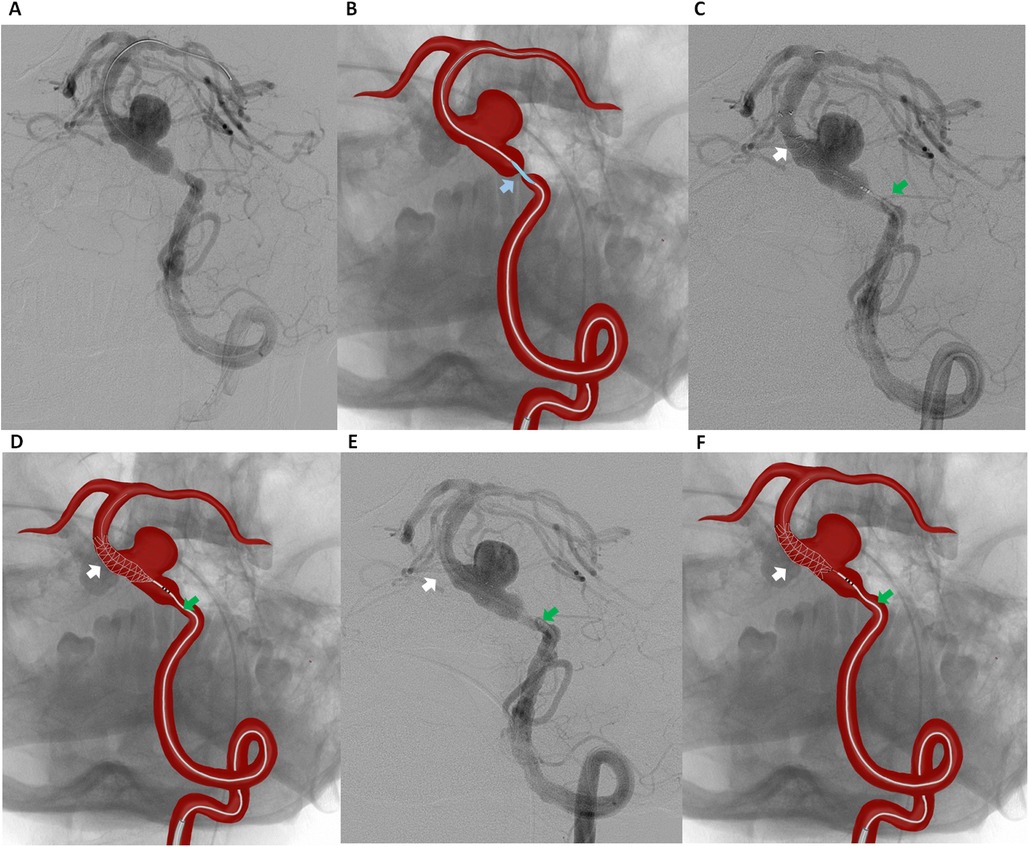

A 6F guiding catheter was advanced into the left vertebral artery via a transfemoral approach. Under roadmap guidance, a Headway 027 microcatheter was navigated across the stenotic segment of the basilar artery over a 0.014-inch Asahi Chikai microwire. A 3.5 mm × 15 mm Accuforce balloon catheter was carefully positioned across the preaneurysmal stenosis. The balloon was inflated up to 8–10 atm under fluoroscopic control to gradually expand the stenotic segment while minimizing the risk of vessel injury or plaque disruption (Figures 2A,B). After maintaining inflation for a few seconds, the balloon was deflated and carefully withdrawn. Immediate DSA confirmed luminal gain in the stenotic segment.

Figure 2. Digital subtraction angiography (A) and schematic illustration (B) of the left vertebral artery showing balloon angioplasty of the preaneurysmal critical stenosis of the basilar artery (blue arrow indicating the accuforce 3.5 mm × 15 mm balloon catheter). Digital Subtraction Angiography (C) and schematic illustration (D) showing flow diverter placement from the middle third of the basilar artery (white arrow indicating the FredX 4.00 mm × 20 mm flow diverter, green arrow indicating the Headway-027 microcatheter). Digital Subtraction Angiography (E) and schematic illustration (F) of the left vertebral artery after stent (FredX 4.00 mm × 20 mm) deployment.

Following successful angioplasty, our initial plan was to deploy a FD for aneurysm embolization. However, FD were not available in our setting at the time. Therefore, a telescopic stent deployment strategy was chosen to ensure complete coverage of the aneurysm neck. The parent vessel measured 4.05 mm proximally and 4.12 mm distally to the aneurysm neck. A FredX 4.00 mm × 20 mm FD was carefully navigated and deployed from the middle third of the basilar artery using a Headway-027 microcatheter, ensuring optimal coverage of the aneurysm neck while aiming to maintain perforator patency (Figures 2C–F).

Given the occlusion of the contralateral vertebral artery and the absence of collateral circulation via the communicating arteries, a second FD with coverage of the stenotic segment was deployed. A second Pipeline 4.00 mm × 20 mm FD was implanted in a telescopic fashion, extending from the middle portion of the previously placed FredX 4.00 mm × 20 mm stent and involving the stenotic segment (Figures 3A,B).

Figure 3. Digital subtraction angiography (A) and schematic illustration (B) showing telescopic placement of a second flow diverter (pipeline 4.00 mm × 20 mm) extending from the middle portion of the previously placed fredX 4.00 mm × 20 mm stent (white arrow indicating the fredX 4.00 mm × 20 mm flow diverter, violet arrow indicating the pipeline 4.00 mm × 20 mm). Digital Subtraction Angiography (C) and schematic illustration (D) showing a “Stent-within-a-Stent” placement of a third flow diverter, FredX 3.50 mm × 22 mm (orange arrow), extending from the middle portion of the previously placed FredX 4.00 mm × 20 mm stent (white arrow) to the middle portion of the previously placed Pipeline 4.00 mm × 20 mm stent (violet arrow). Digital Subtraction Angiography: Frontal (E) and lateral (F) views of the left vertebral artery immediately after surgery.

Post-deployment DSA demonstrated instability due to shortening of the first two 4.0 mm FDs. The first stent was undersized relative to the vessel diameter, resulting in shortening and covering approximately 75% of the aneurysm neck. The second stent 4.0 mm stent, placed in the widest vessel segment, also demonstrated shortening. To stabilize the construct and prevent potential migration into the aneurysm, a third 3.5 mm FD (FredX 3.50 mm × 22 mm) was deployed in a stent-within-a-stent configuration (Figures 3C,D) using a Headway-027 microcatheter navigated through the previously placed stents under roadmap guidance.

Post-procedural angiography confirmed successful reconstruction of the BA. DSA immediately after the procedure demonstrated delayed contrast filling of the aneurysm (O’Kelly-Marotta grade B) without evidence of endoleak or significant in-stent stenosis (Figures 3E,F). The patient was discharged on the second postoperative day without neurological deficits. At discharge, dual antiplatelet therapy was prescribed, consisting of Ticagrelor (90 mg twice daily) for 6 months and Aspirin (100 mg daily) for long-term therapy. The patient was already receiving Atorvastatin 20 mg daily, which had been prescribed by the cardiologist prior to admission.